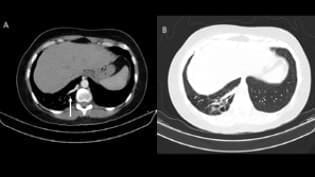

No había trastornos de oxigenación ni de restricción pulmonar, y el estudio imagenológico mostraba en LID una zona de hiperinsuflación y atrapamiento de aire del parénquima perilesional, bronquiectasias, cavidades aéreas con paredes gruesas con dimensiones de 31 x 24 mm y una estructura vascular prominente extendiéndose hacia la periferia de la lesión, con origen directamente de la aorta a nivel de la unión toracoabdominal, a favor de secuestro pulmonar (figura 1).

Figura 1. Tomografía Computarizada – AngioTAC. (A) Ventana mediastinal. Flecha blanca, vaso aberrante nutricio de secuestro pulmonar, con origen en aorta torácica descendente. (B) Ventana pulmonar. Secuestro pulmonar en lóbulo inferior derecho.